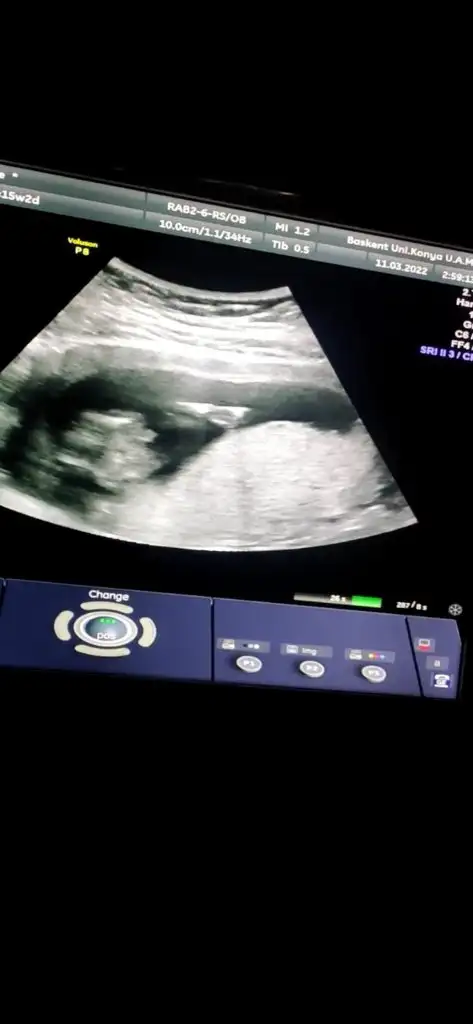

Ben bişey anlayamadım nuba göre benim ne oluyor acabaCumartesi cinsiyet öğreneceğim o yüzden bütün teorileri araştırırken bu karşıma çıktı bana mantıklı geldi gibişöyle ki omurgadan popoya doğru giden çizgi sonda yukarı doğru çıkıyorsa erkek, düz gidiyorsa kız oluyormuş fotoğraf ekleyeceğim orda daha ayrıntılı gösteriyor

Dr da öyle dedi emin olamadı alttan bakınca da kıza benziyor dediAyy maşallah ne güzel çıkmışsanki şu işaretlediğim yerde yukarı doğru bir çıkıntı varmış gibi geldi bana Öyle olunca da erkek deniyor ama bilemiyorum tamamen benim yorumum